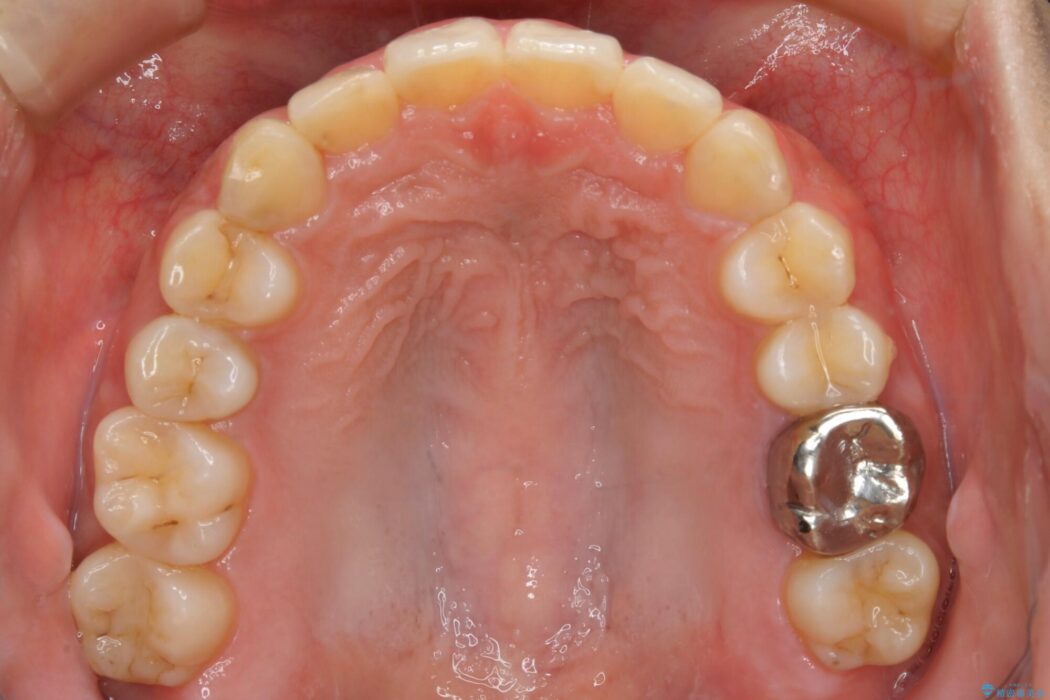

口ゴボに加えて歯列のガタガタを改善したいと来院されました。

患者様のご希望によりインビザライン装置での治療を行いました。

インビザラインは歯を後ろへ動かす動き、非抜歯での矯正治療が得意なため、ワイヤー装置では難しいケースでも対応できる場合があります。

矯正治療において歯並びを整えるためにはスペースが必要になります。

抜歯・歯列幅の拡大・IPR(歯と歯の間を少し削って小さくする)・歯の後方移動などでそのスペースを確保します。

程度にもよりますが口元を下げる治療というと抜歯治療を思い浮かべると思いますが、インビザラインは抜歯をせずとも他の3種類の方法を効率よく活用し治療ができます。